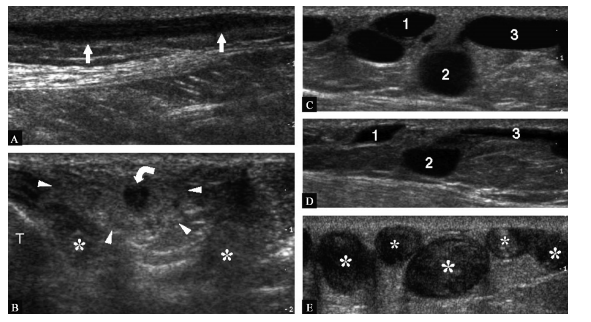

不同的病例。A,B. 形成血栓的大隐静脉(箭头)12~5MHz超声纵断面(A)和横断面(B)图像。注意形成血栓的静脉周围反应性的皮下脂肪(箭头端)强回声。为比目鱼肌;T. 胫骨。C,D. 一例浅静脉曲张(1~3)的患者12~5MHz超声探头未加压(C)及加压时(D)获取的横断面图像。探头加压是评价静脉系统状态的有用方法。在本例中,浅静脉是开放的,可完全压闭。E. 一例浅静脉曲张血栓形成( )的患者12~5MHz超声横断面挤压远端小腿的远端静脉增宽试验有助于评价这些静脉的状况。形成血栓的浅静脉常为一圈高回 声 的 皮 下 脂 肪 所 包 绕 (图 一B)。深静脉血栓的患者如有静脉瓣的损害,则可导致静脉功能不全及皮下组织内静脉曲张,呈走行于皮下组织内的纡曲的无回声管道(图一C~E)。